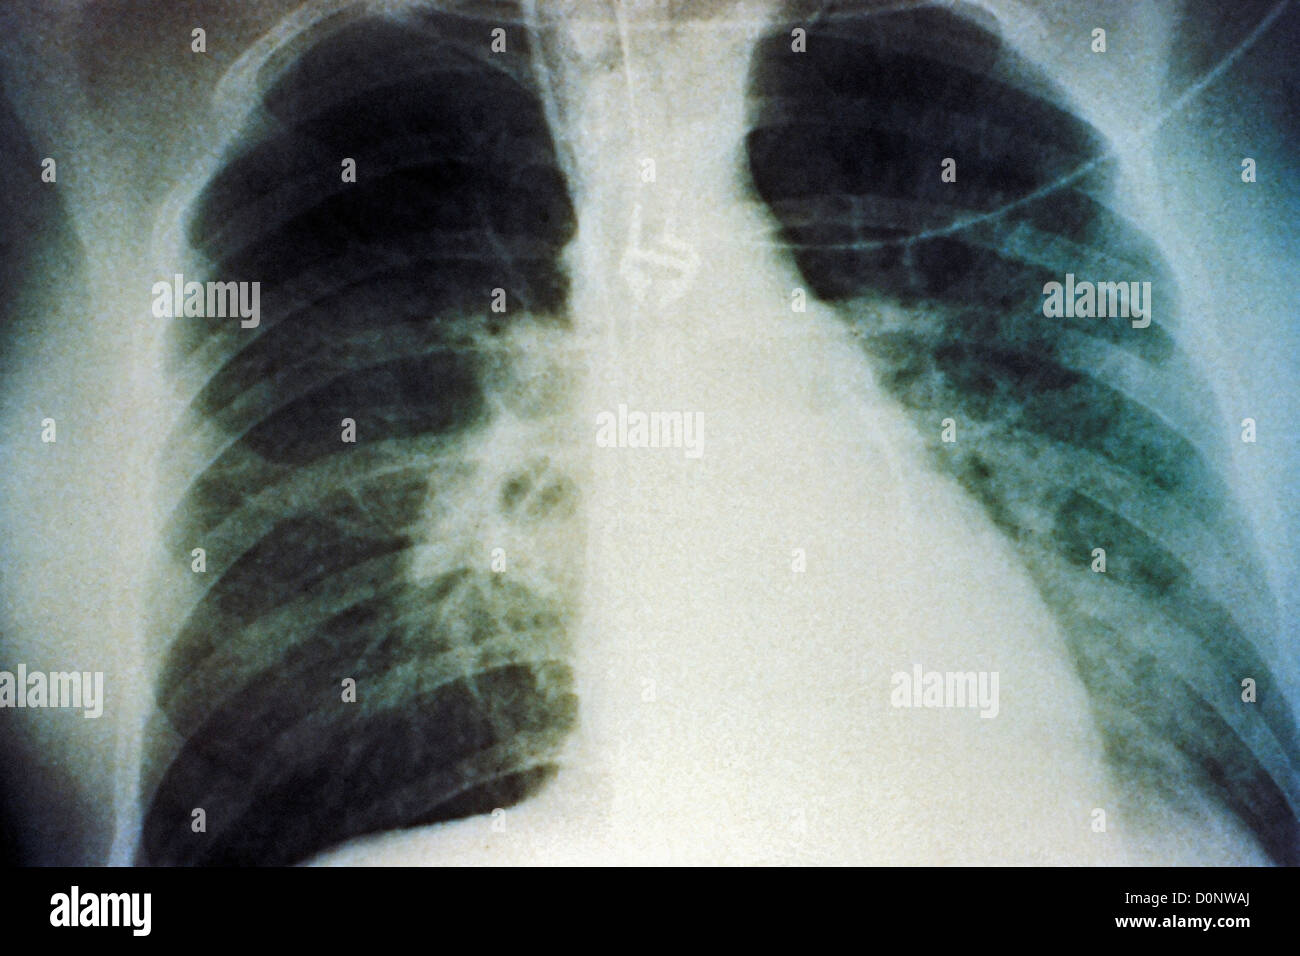

RMPF833F–Mise en scène mi-épanchement pulmonaire bilatéral en raison de syndrome pulmonaire à hantavirus (SPH), révélée dans l'AP La radiographie du thorax, 1994. Image courtoisie Centres for Disease Control (CDC) / D. Loren Ketai, M.D. ()

RMPF8351–Premières étapes de l'épanchement pulmonaire bilatéral en raison de syndrome pulmonaire à hantavirus (SPH), révélée dans l'AP La radiographie du thorax, 1994. Image courtoisie Centres for Disease Control (CDC) / D. Loren Ketai, M.D. ()

RMD0NWAJ–Cette radiographie pulmonaire révèle la mi-monté en raison d'épanchement pulmonaire bilatéral syndrome pulmonaire à hantavirus ou radiologique de la SPLI.

RMPF834T–Mise en scène mi-épanchement pulmonaire bilatéral en raison de syndrome pulmonaire à hantavirus (SPH), révélée dans l'AP La radiographie du thorax, 1994. Image courtoisie Centres for Disease Control (CDC) / D. Loren Ketai, M.D. ()